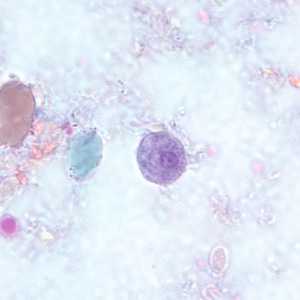

E. coli cysts stained with trichrome.

Figure A: Immature cyst of E. coli, stained with trichrome. Notice the presence of only two nuclei, and a large glycogen vacuole.

Figure B: Mature cyst of E. coli, stained with trichrome. Five nuclei are visible in this focal plane.

Figure C: Mature cyst of E. coli, stained with trichrome. In this specimen, at least five nuclei are visible in the shown focal plane.

Figure D: Mature cyst of E. coli, stained with trichrome. In this specimen, at least five nuclei are visible in the shown focal plane.

Figure E: Mature cyst of E. coli, stained with trichrome. This figure and Figure F represent the same cyst shown in two different focal planes. Eight nuclei can be seen between the two focal planes. Also, above the cyst in this figure, a trophozoite of Endolimax nana can be seen.

Figure F: Mature cyst of E. coli, stained with trichrome. This figure and Figure E represent the same cyst shown in two different focal planes. Eight nuclei can be seen between the two focal planes.